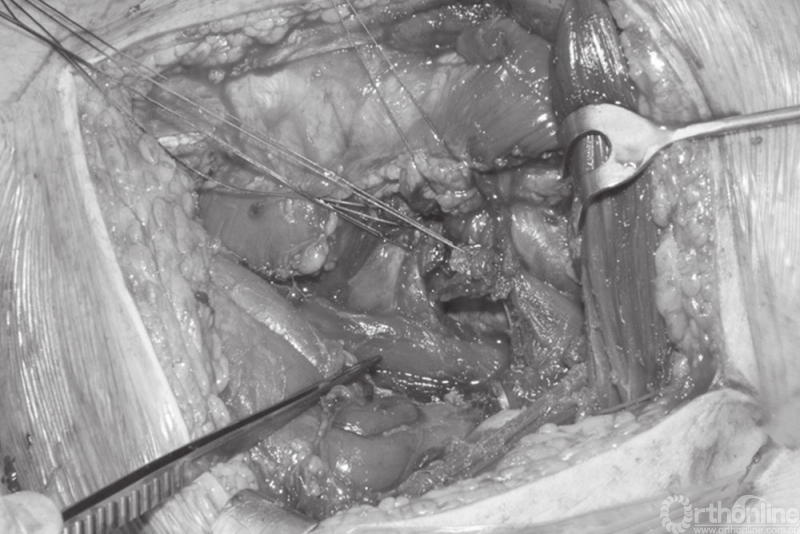

患者取侧卧位,行KL入路治疗髋臼后壁骨折。采用打入坐骨结节的Schanz针来纠正后柱骨块的移位和外旋畸形,在伸髋屈膝位时应注意保护坐骨神经。术中必要时可适度牵拉骨折块以达到理想的复位,并对骨折块进行必要的清理。

利用2枚螺钉联合骨盆复位钳完成后柱

有种有效的复位策略是在骨折的两侧分别打入一枚螺钉,通过相对应的复位钳进行辅助复位固定。随着复位钳逐渐夹紧,骨折移位被纠正并复位(图24.17)。骨折平移和旋转移位也可通过这种组合复位办法进行纠正。